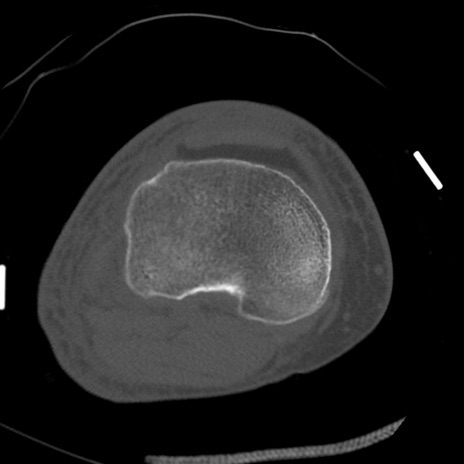

症例28 右膝関節CT(横断像)

右膝関節CT